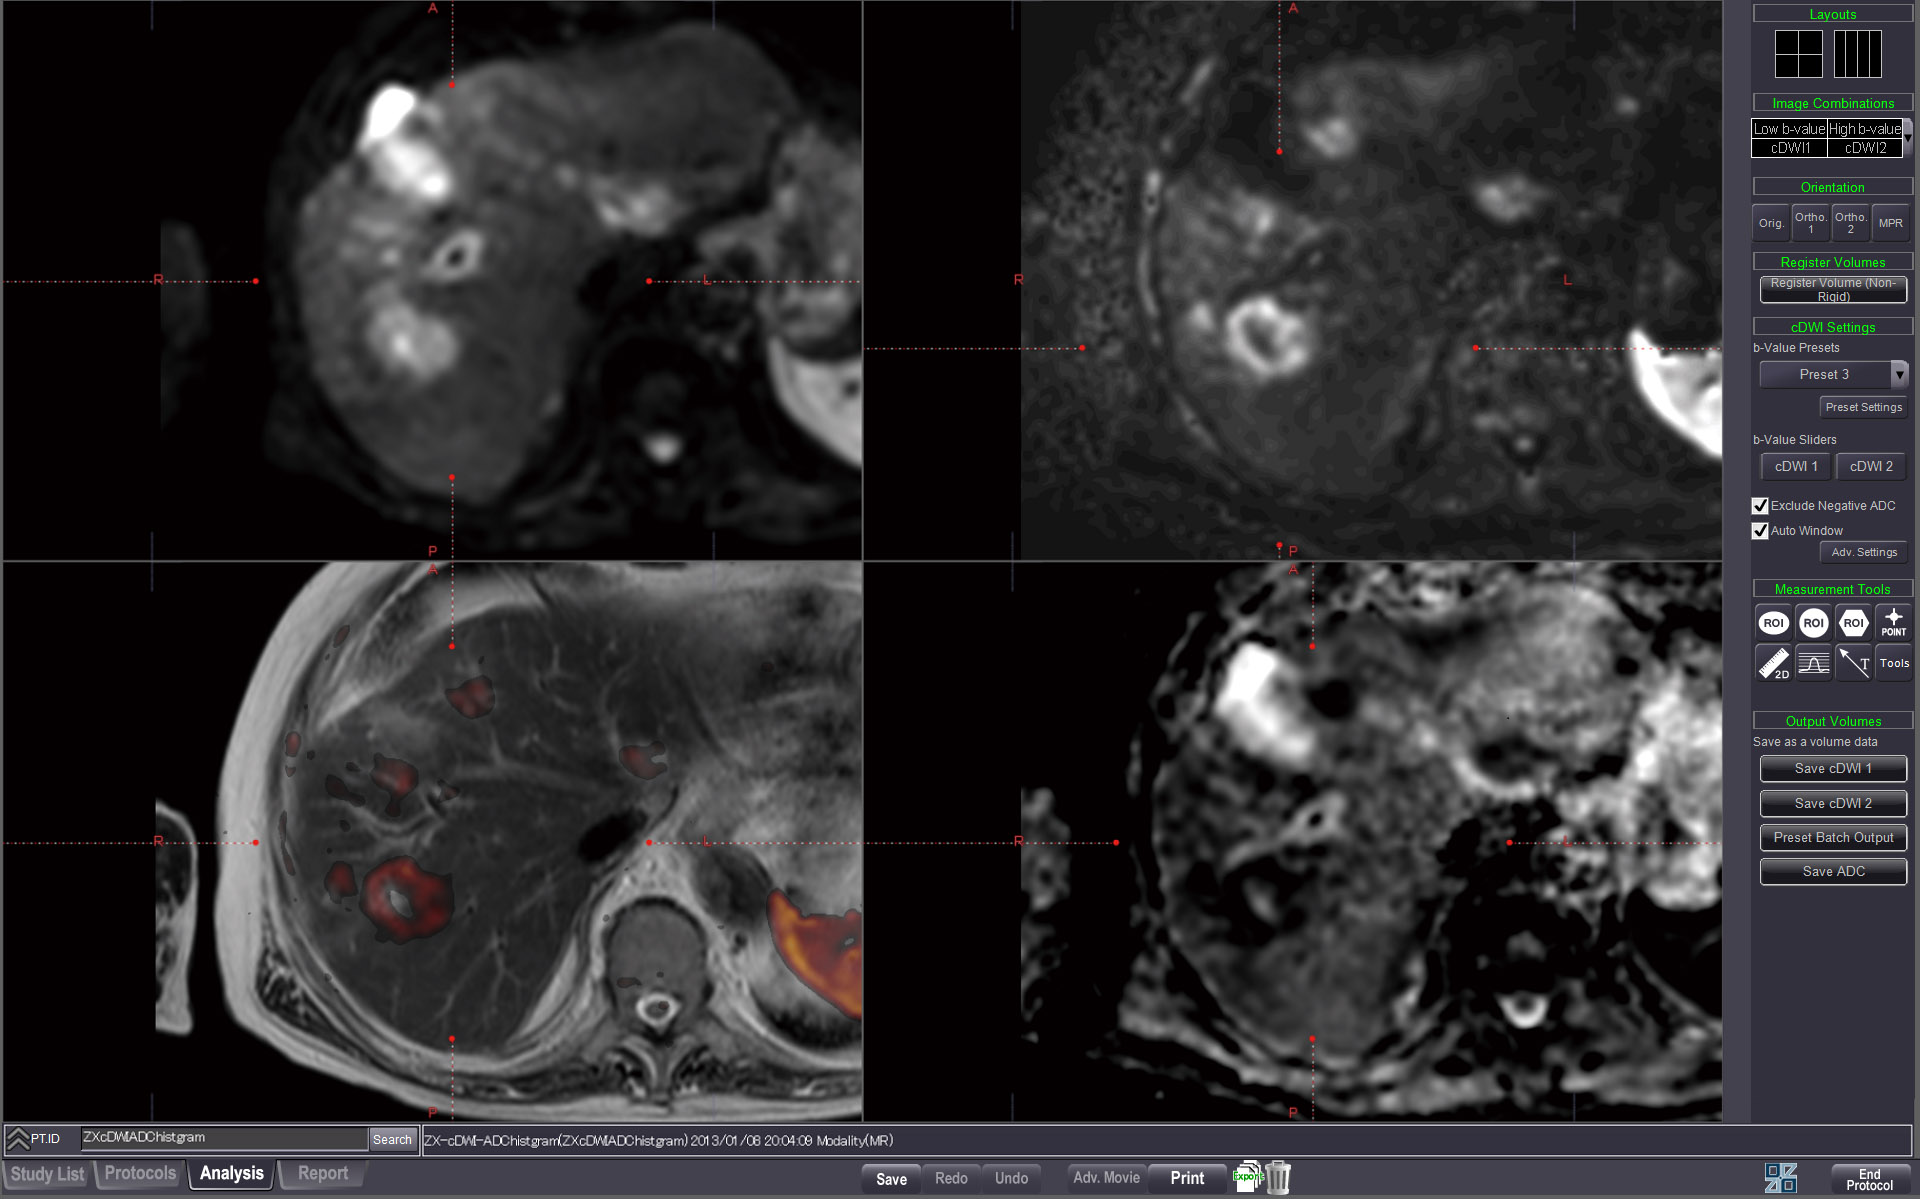

COMPUTED DWI

Creating specific b-value images and using the calculated ADC map enables comprehensive analysis of lesion and diffusion characteristics.